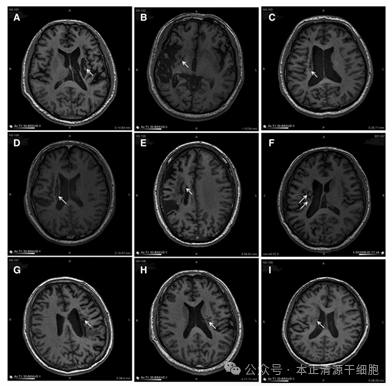

案例1

合作医院在《干细胞转化医学》(Stem Cells Translational Medicine)杂志上公布,干细胞回输有助于脑卒中偏瘫患者运动功能的恢复。9名年龄在3065岁之间的偏瘫患者参与了这项临床研究,他们在中风后5-24个月接受干细胞回输,干细胞被回输至脑内梗塞灶附近。影像学研究的结果表明,干细胞输入区出现了新的神经组织,这也证明了干细胞干预偏瘫性脑卒中拥有一定的临床益处。

通过24个月的随访临床结果,显示了相对于基线的分数变化。

图片

9例患者的影像学显示病变区域的组织都发生了明显变化。回输到脑内梗塞病灶的干细胞,通过分化为神经系统的各类细胞、分泌营养因子,促进神经和血管再生,修复受损的血-脑脊液屏障,减轻炎性反应等促进脑梗死患者的神经功能恢复,让9例临床患者偏瘫的症状得到了明显改善。